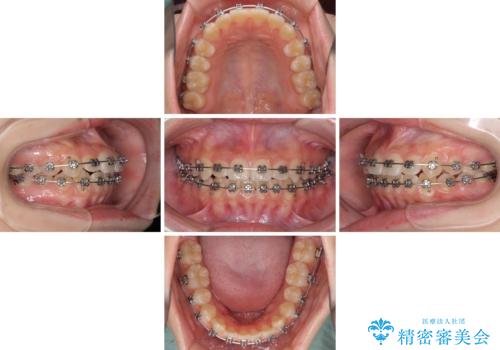

前歯のクロスバイト メタル装置での矯正治療

- 前歯のクロスバイトを気にして来院された患者様です。

前歯の叢生を解消するスペースを獲得するために上顎左右の親知らずを抜歯し、メタルブラケットにて矯正治療を行うこととしました。

当初は1年半程度の治療期間を想定していましたが、上下の正中を合わせていく過程で奥歯の咬みにくさが続いてしまい、2年以上の治療期間を要することとなりました。